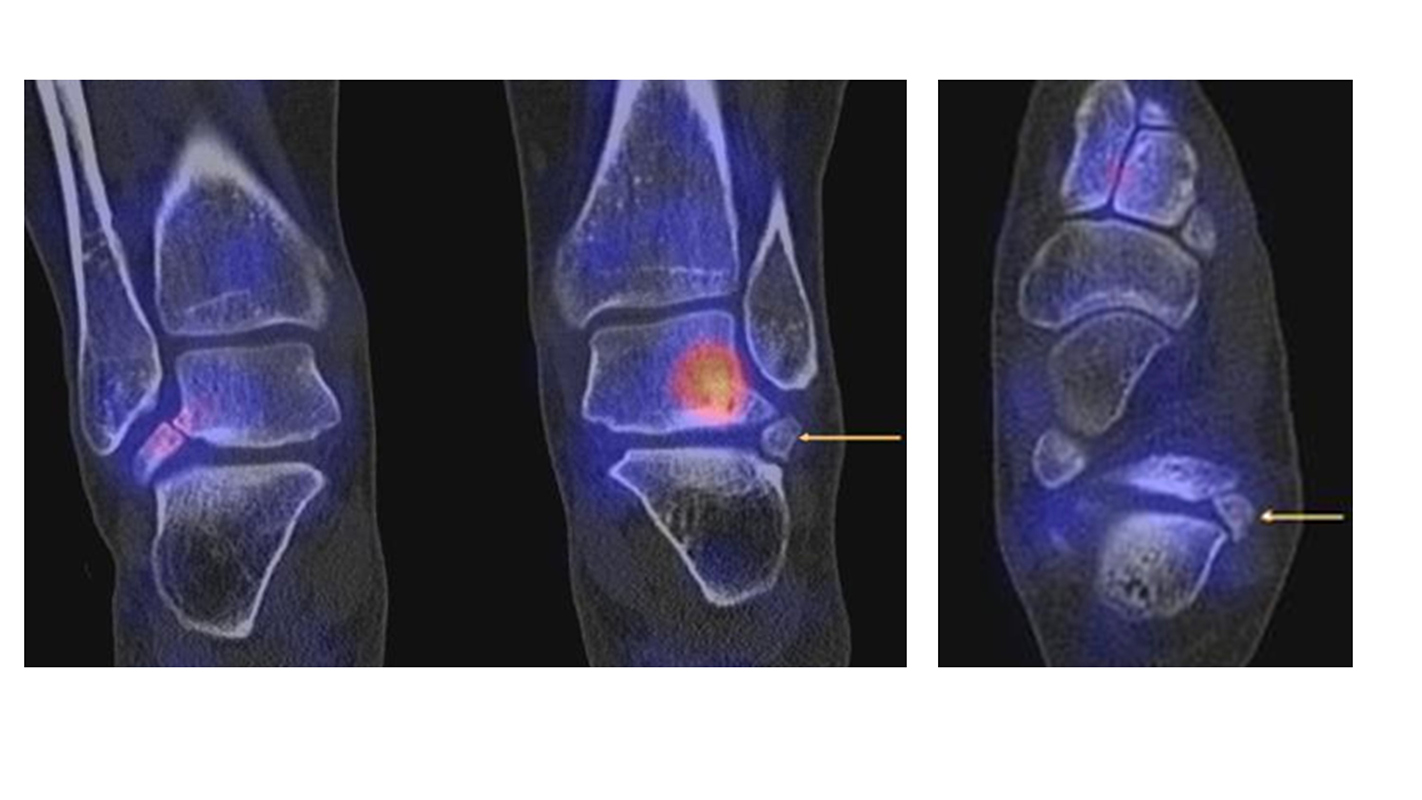

In Abbildung 3.4. ist ein typisches Beispiel für ein symptomatisches Os trigonum dargestellt.

Zum Lesen der Bildbeschreibung und zur Vollansicht bitte das Bild anklicken. Bild: H. C. Rischke

In Abbildung 3.5. Bilder einer Patientin mit einem Talus secundarius beiderseits (auf der linken Seite mit einem Pfeil markiert). Die teilweise mit angeschnittene linksseitige Anreicherung im Talus stammt von einer postero-lateraler Stressreaktion infolge eines akzessorischen Knochenelementes lateral des Processus posterior tali. Die Bilder hierzu werden im Kapitel "SPECT/CT im direkten Vergleich mit der MRT" gezeigt.

Auch Stressreaktionen am unteren Sprunggelenk können mit Hilfe der SPECT/CT exakt lokalisiert und differenziert werden.

Eine konservative Therapie bei einem Sinus tarsi Syndrom kann bei unauffälliger Anatomie erfolgreich sein 35, wobei die konventionelle Bildgebung limitiert ist. So kann ein mit Hilfe der SPECT/CT erbrachter eindeutiger Nachweis eines Stress-verursachenden hypermetabolen Ossikels im Sinus tarsi auf den Erfolg einer operativen Therapie hinweisen.

Einen solchen Fall zeigt die Abbildung 3.6., der bei uns untersucht wurde. Bei diesem Patienten bestanden chronisch persistierende Schmerzen seit 3 Jahren infolge einer Distorsion. Zwei vorhergehende MRT-Untersuchungen 1 Jahr und 2 Jahre nach dem Trauma waren nicht wegweisend. Wegen persistierender Beschwerden wurde uns der Patient zum SPECT/CT zugewiesen. Nach operativer Entfernung des Ossikels war der Patient dauerhaft beschwerdefrei.

Achong beschreibt einen gleichartigen Fall mit einem mittels SPECT/CT im Sinus tarsi identifiziertes Ossikel im Sinus tarsi mit einer Größe von 8 mm 36, bei dem eine vorangehende MRT-Untersuchung gleichfalls nicht wegweisend war, weswegen eine SPECT/CT angefertigt wurde.

Auch Boulet et al. publizierten einen ähnlichen Fall 37. Sie beschreiben den Fall eines 45-jährigen Sportlers (Basketballer) mit chronischen Sprunggelenkschmerzen und lateraler Sprunggelenk-Instabilität bei Zustand nach wiederholten Sprunggelenks­distorsionen. Konservative Maßnahmen (Tape-Verbände, Physiotherapie) waren erfolglos. Es bestanden neben der lateralen Sprunggelenk-Instabilität auch ein Druckschmerz am Sinus tarsi. Im Röntgen konnte ein Ossikel im Sinus tarsi abgegrenzt werden, im MRT ein Längsriss der Peroneaus brevis Sehne, ein Ödem in dem Ossikel und im Tarsus. Im SPECT/CT zeigte sich korrespondierend ein deutlicher Hypermetabolismus in dem Ossikel. Zunächst erfolgte eine operative Stabilisierung der Sprunggelenk-Instabilität, welche jedoch keine Beschwerdefreiheit erbrachte. Erst die Resektion des Ossikels führte zur Beschwerdefreiheit.

Pathologien im Bereich des Processus anterior des Calcaneus bzw. im Bereich der Gelenkräume zwischen Calcaneus, Talus, Os naviculare und Cuboideum können mit Hilfe der SPECT/CT dargestellt und differenziert werden. Differenzialdiagnosen wären zum Beispiel eine Fraktur des Processus anterior calcanei, ein symptomatischer Os calcaneus secundarius oder eine Coalitio (vgl. Abbildung 4.1.a und b) 38. Abbildung 3.7. demonstriert den Fall einer Patientin mit einer aktivierten Stresssituation kranial an der Facies articularis calcanei im Bereich eines partiell synostosierten Os calcaneus secundarius.